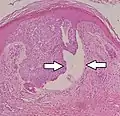

Nodular basal-cell carcinoma

.jpg.webp)

Nodular basal-cell carcinoma (also known as "classic basal-cell carcinoma") accounts for between 50% and 80% of all BCC.[2] It most commonly occurs on the sun-exposed areas of the head and neck.[2] Histopathology shows aggregates of basaloid cells with well-defined borders, showing a peripheral palisading of cells and one or more typical clefts.[17] Such clefts are caused by shrinkage of mucin during tissue fixation and staining.[18] Central necrosis with eosinophilic, granular features may be also present, as well as mucin. The heavy aggregates of mucin determine a cystic structure. Calcification may be also present, especially in long-standing lesions.[17] Mitotic activity is usually not so evident, but a high mitotic rate may be present in more aggressive lesions.[17] Adenoidal BCC can be classified as a variant of NBCC, characterized by basaloid cells with a reticulated configuration extending into the dermis.[17]

Cleft.